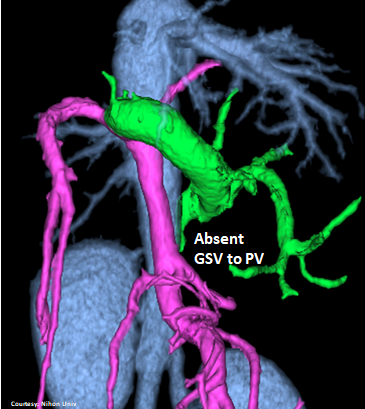

Does the GASTROSPLENIC VEIN (GSV) enter the PORTAL VEIN (PV)?

(Absent GSV)

Does the GASTROSPLENIC VEIN (GSV) enter the CAUDAL VENA CAVA (CdVC) directly?

“LGC +PancV -GSV” Left Gastro-Caval Shunt with Pancreatic Vein contribution and absent Gastro-splenic vein (GSV does not enter PV)

Courtesy: Nihon Univ